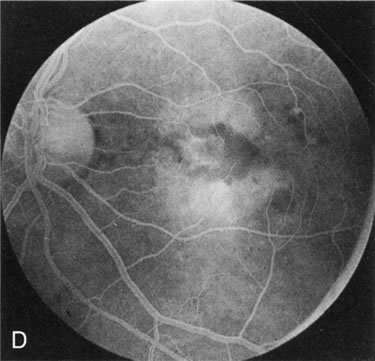

Fig. 1. Retinitis pigmentosa. A. A typical area of bone spicule pigmentation. B. Diffuse dye leakage is apparent throughout the posterior pole. C. The early angiogram shows dilated and irregular retinal radial peripapillary capillaries and perifoveal retinal capillaries. D. Leakage from these vessels are evident in the late angiogram.

Of more clinical importance is the role of FA in the diagnosis and treatment of cystoid macular edema (CME) (Fig. 1C and D). Stereoscopic FA indicates that the leakage, which may be diffuse or have the typical petaloid stellate appearance of CME, can come from the perifoveal retinal capillaries, from the choroid through the RPE, or from a combination of both sources.4 With the recent suggestion that CME in RP may be successfully treated with acetazolamide,5, 6 FA is thus important to document the diagnosis of CME, establish the origin(s) of leakage, and follow patients during and after therapy.